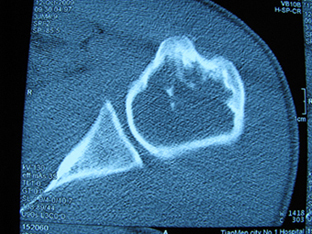

标题: X6404B:肱骨骨质破坏(CT片) [打印本页]

标题: X6404B:肱骨骨质破坏(CT片)

男,50岁,左肩部轻微疼痛,活动不便5个月就诊,近十天加重,无红肿热,间断理疗治疗无好转,既往5个月前左肩轻微拉伤史

骨巨?动脉瘤样骨囊肿?

内生软骨瘤。

内生软骨瘤。

内生软骨瘤?-----------

年纪大了,先要排除转移瘤。

髓腔内软组织肿块并斑片状钙化,考虑高分化软骨肉瘤可能性大。

考虑骨巨或动脉瘤样骨囊肿。

内生软骨瘤可能性大,期待结果。

孤立性骨囊肿。

内生软骨瘤可能性大

其内可见钙化,考虑软骨源性肿瘤,内生软骨瘤可能

但由于年龄较大,恶性软骨肉瘤待排

肱骨头内巨大软组织肿块并斑片状钙化,内生软骨瘤?骨巨细胞瘤?软骨粘液样纤维瘤?期待结果!

髓腔内软组织肿块并斑片状钙化,考虑高分化软骨肉瘤可能性大。

内生软骨瘤可能性大

肱骨头内巨大软组织肿块并斑片状钙化,内生软骨瘤?骨巨细胞瘤?软骨粘液样纤维瘤?期待结果

考虑内生软骨瘤?骨巨细胞瘤?

内生软骨瘤?骨巨细胞瘤?

先要排除转移瘤。